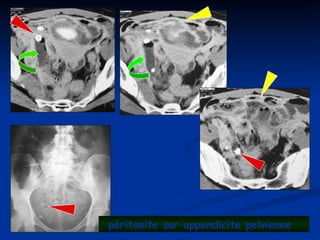

péritonite sur appendicite pelvienne

 Les péritonites

 En 1 temps : tableau d’app typique puis aggravation

En 1 temps : tableau d’app typique puis aggravation

 En 2 temps : tableau d’app typique, accalmie, puis aggravation

En 2 temps : tableau d’app typique, accalmie, puis aggravation

 En 3 temps : app, plastron, abcès,péritonite

En 3 temps : app, plastron, abcès,péritonite

 Clinique

Clinique

 Douleurs diffuses

Douleurs diffuses

 Température à 40°

Température à 40°

 Contracture

Contracture

 TR,TV

TR,TV

 Etat de choc??

Etat de choc??